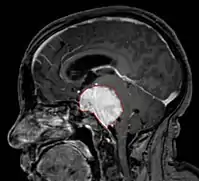

• MRI

• Preferred imaging because it can show dural origin

• Dural tail sign seen in about two-thirds: characteristic marginal thickening that tapers peripherally along the dura

• Isointense on T1, hyperintense (usually homogeneously) on T2, strong enhancement with IV contrast